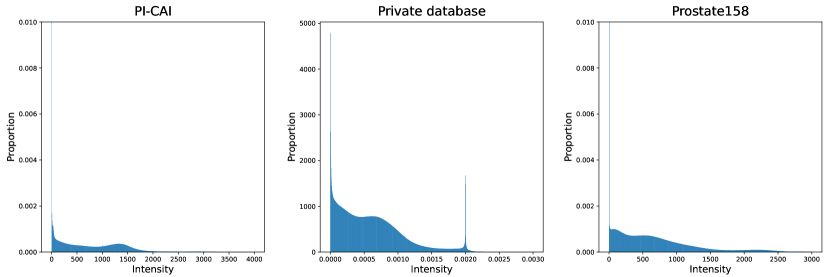

Both T2-weigthed (T2w) and apparent diffusion coefficient (ADC) MR maps were used as input channels. The latter modality was registered to the former, all images were resampled to a mm3 pixel size and cropped to volumes. Images intensities were linearly normalized into the range [0, 1] for each patient and each modality. More details about these datasets can be found on Appendices A and B, including lesion volume distributions and histograms of intensities for T2-weighted imaging and ADC maps.

Appendix B Characteristics of MRI modalities for each database